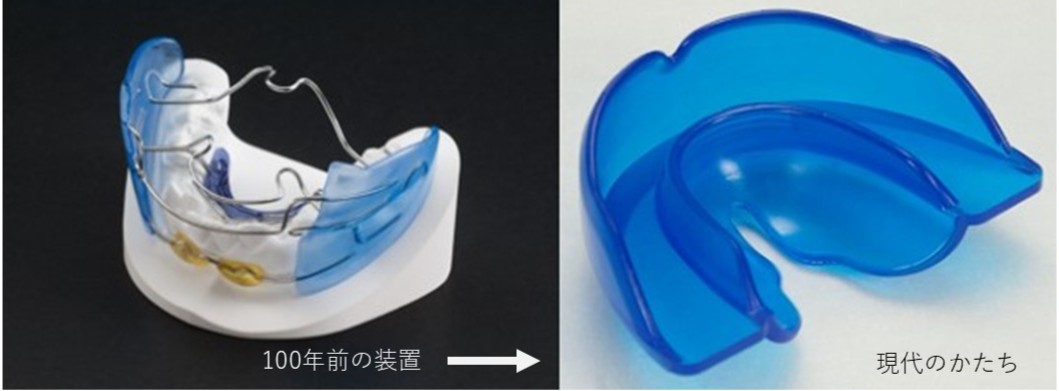

資料は、写真とレントゲンです。歯型取りをする場合もあります。

セファロ(側方レントゲン)で診断します。問題ないようでしたら矯正治療の開始です。